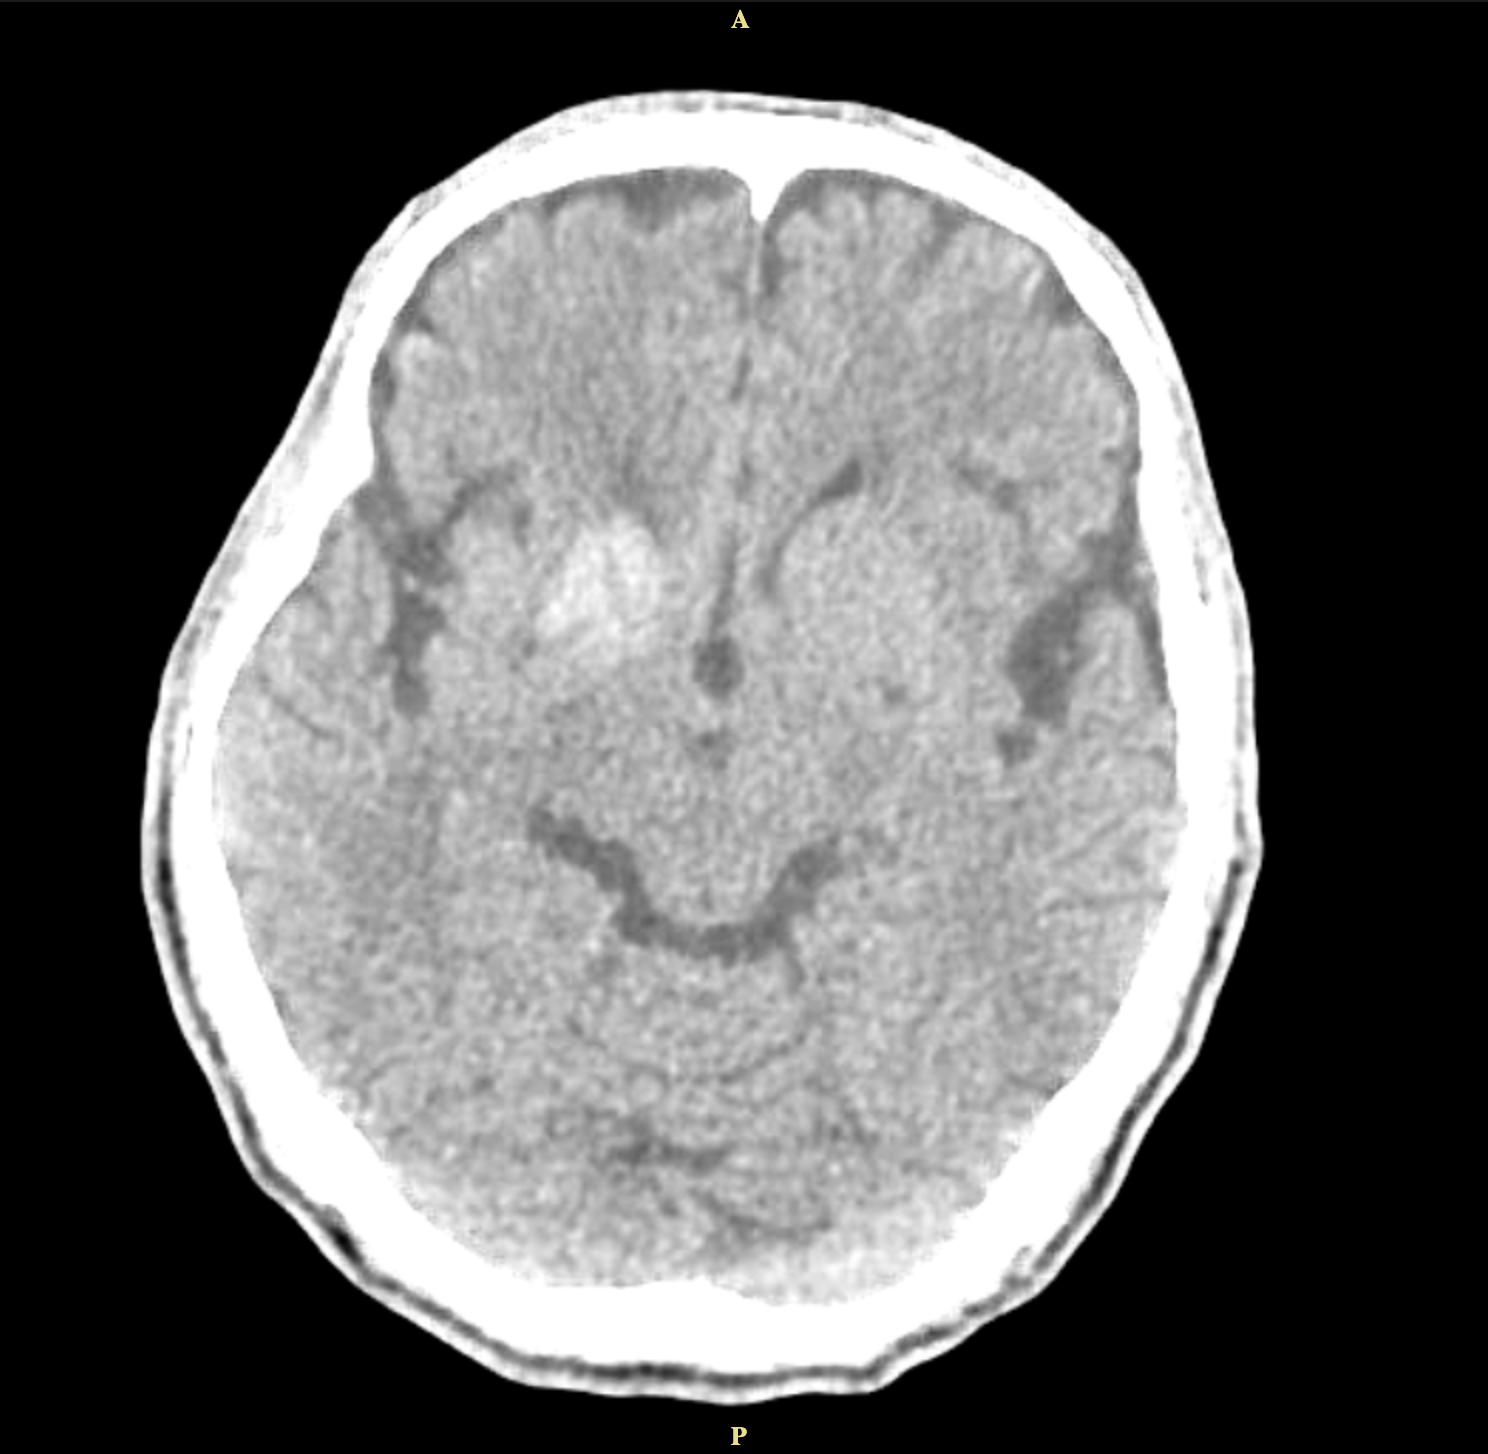

Method: A 62-year-old man with uncontrolled diabetes presented with left-sided involuntary movements and slurred speech. His blood glucose was elevated at 576mg/dl, and CT imaging showed hyperdensity in the right caudate and lentiform nuclei. His condition improved with glycemic control, and antichoreic medications were not needed.

Results: This condition occurs in about 1 in 100,000 individuals. Diagnosis relies on neuroimaging, particularly CT or MRI, which reveal basal ganglia lesions, often in the putamen or caudate nucleus. The hallmark finding is striatal hyperintensity without mass effect, sparing the internal capsule. CT has a sensitivity of 78%, and MRI 95% for detecting diabetic striatopathy, with resolution times ranging from 10 to 60 days.

Conclusion: The classic triad for diabetic striatopathy includes poor glycemic control, unilateral striatal hyperdensity on CT imaging, and contralateral choreic movements. Treatment involves achieving euglycemia and managing chorea. Symptom resolution can occur within 2–14 days, with glycemic control alone resolving symptoms in 25% of cases. Adding anti-choreic medications increases resolution to 76%. He continued intensive insulin therapy for 6 months, leading to improvement and eventual resolution of left-sided movement.

Figure 1.1